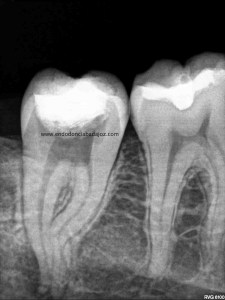

Sistemas de Conductos de un 4.7

Nos remiten a  la clínica una pieza 4.7, con necrosis pulpar y afectación periodontal, periodontitis apical:

La anatomía de los conductos nos hacia sospechar de un caso algo más complicado. Lo más complicado fue mantener la permeabilidad de los conductos. Instrumentamos con sistema rotatorio de Mtwo, mucha irrigación, se usó Irrisafe en los últimos lavajes, y como sistema de obturación usamos Condensación vertical con ola contínua, haciendo un backfilling con la Pistola Obtura II.

(disto)                                                                               (mesio)